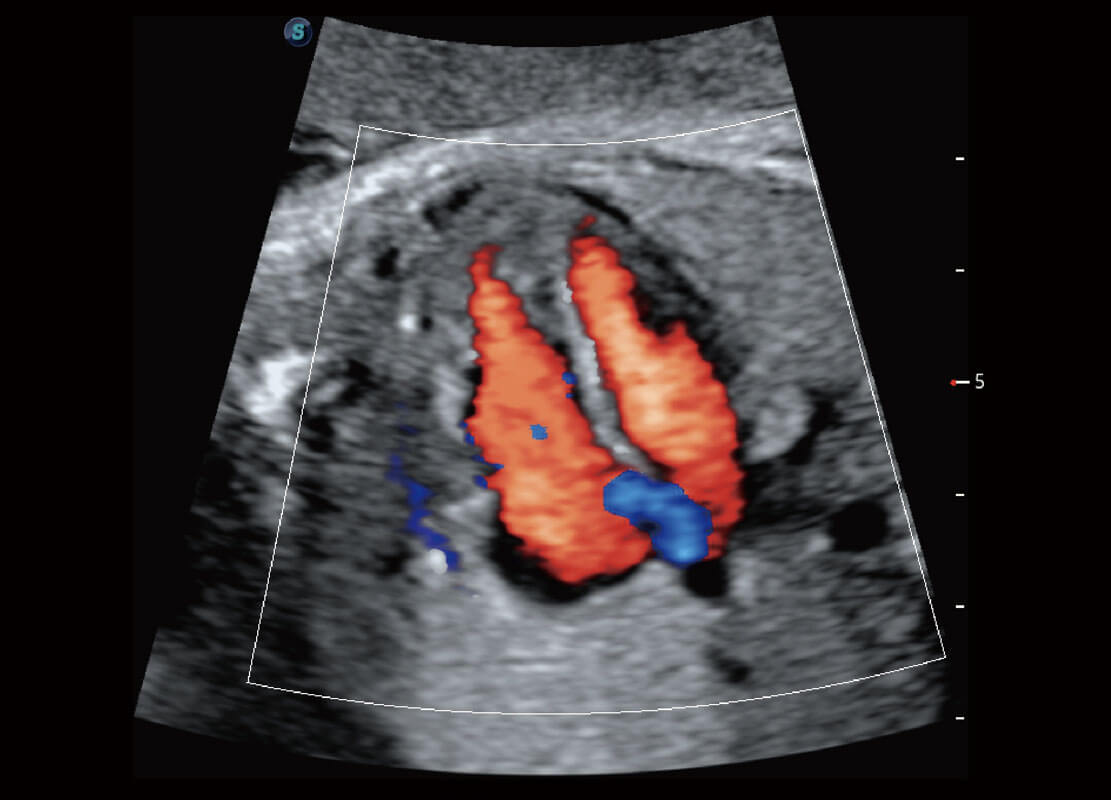

P60優(yōu)異的圖像質(zhì)量搭載專科探頭,在婦科基礎(chǔ)疾病的診斷、卵泡生長(zhǎng)的監(jiān)測(cè)、輸卵管通暢情況的判別等方面為您提供生殖應(yīng)用方案。

腔內(nèi)婦科-宮腔分離

腔內(nèi)婦科-卵巢